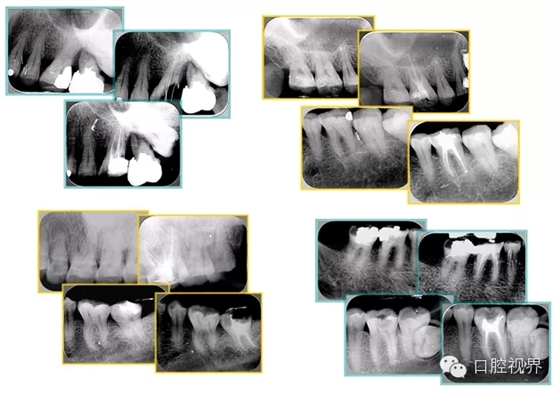

常見(jiàn)不良根管充填物有干髓、塑化、塑化 + 根充和不良根充。

( 1 )干髓。

左圖和上圖為干髓治療后牙齒,齲齒疏通后進(jìn)行根管充填。

( 2 )塑化。

如圖為塑化加根充處理后牙齒 X 線片。

( 4 )不良根充。

6. 鈣化

常見(jiàn)有修復(fù)性鈣化和增齡性鈣化。下面為根管鈣化 X 線片。